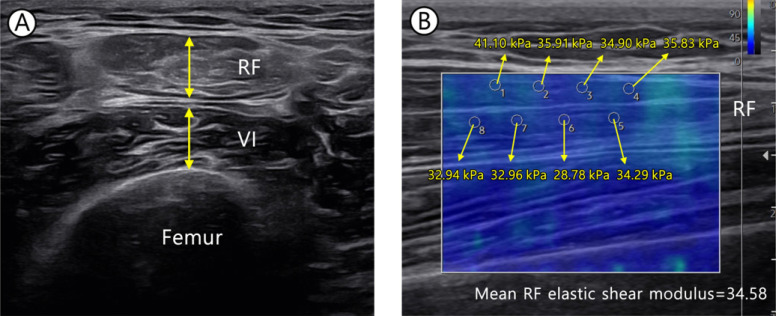

Methods: Thirty hemiplegia patients diagnosed with stroke participated in this study. To evaluate poststroke muscle changes, longitudinal measurement of muscle mass and quality was conducted with bilateral lower limbs. The elastic shear modulus was measured using shear wave elastography and muscle thickness (MT) of rectus femoris, vastus intermedius, vastus lateralis (VL), vastus medialis, tibialis anterior, and gastrocnemius (GCM) muscles. Functional evaluation was performed using Berg Balance Scale (BBS), Five Times Sit to Stand Test (FTSST). Follow-up was performed at discharge. The muscle mass and quality were compared according to time. We analyzed whether muscle quantity and quality were related to function.